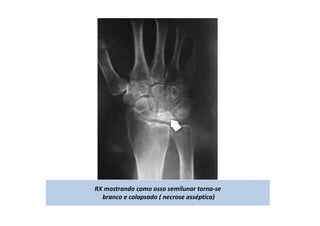

RX mostrando como osso semilunar torna-se

branco e colapsado ( necrose asséptica)